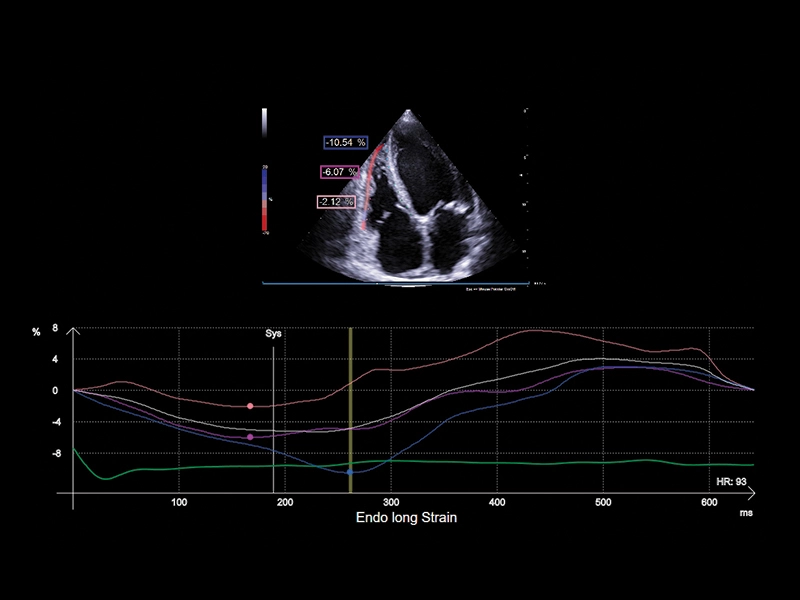

MyLab™C25 - Xstrain

MyLab™C25 - Xstrain

MyLab™9 Platform - XStrain™ 2D speckle tracking technologies for global and regional function

MyLab™9 Platform - XStrain™ 2D speckle tracking technologies for global and regional function

MyLab™Sigma - Left Ventricle XStrain 2D analysis

MyLab™Sigma - Left Ventricle XStrain 2D analysis

MyLab™X5 - XStrain

MyLab™X5 - XStrain

MyLab™X6 - XStrain

MyLab™X6 - XStrain

MyLab™X7 - XStrain

MyLab™X7 - XStrain